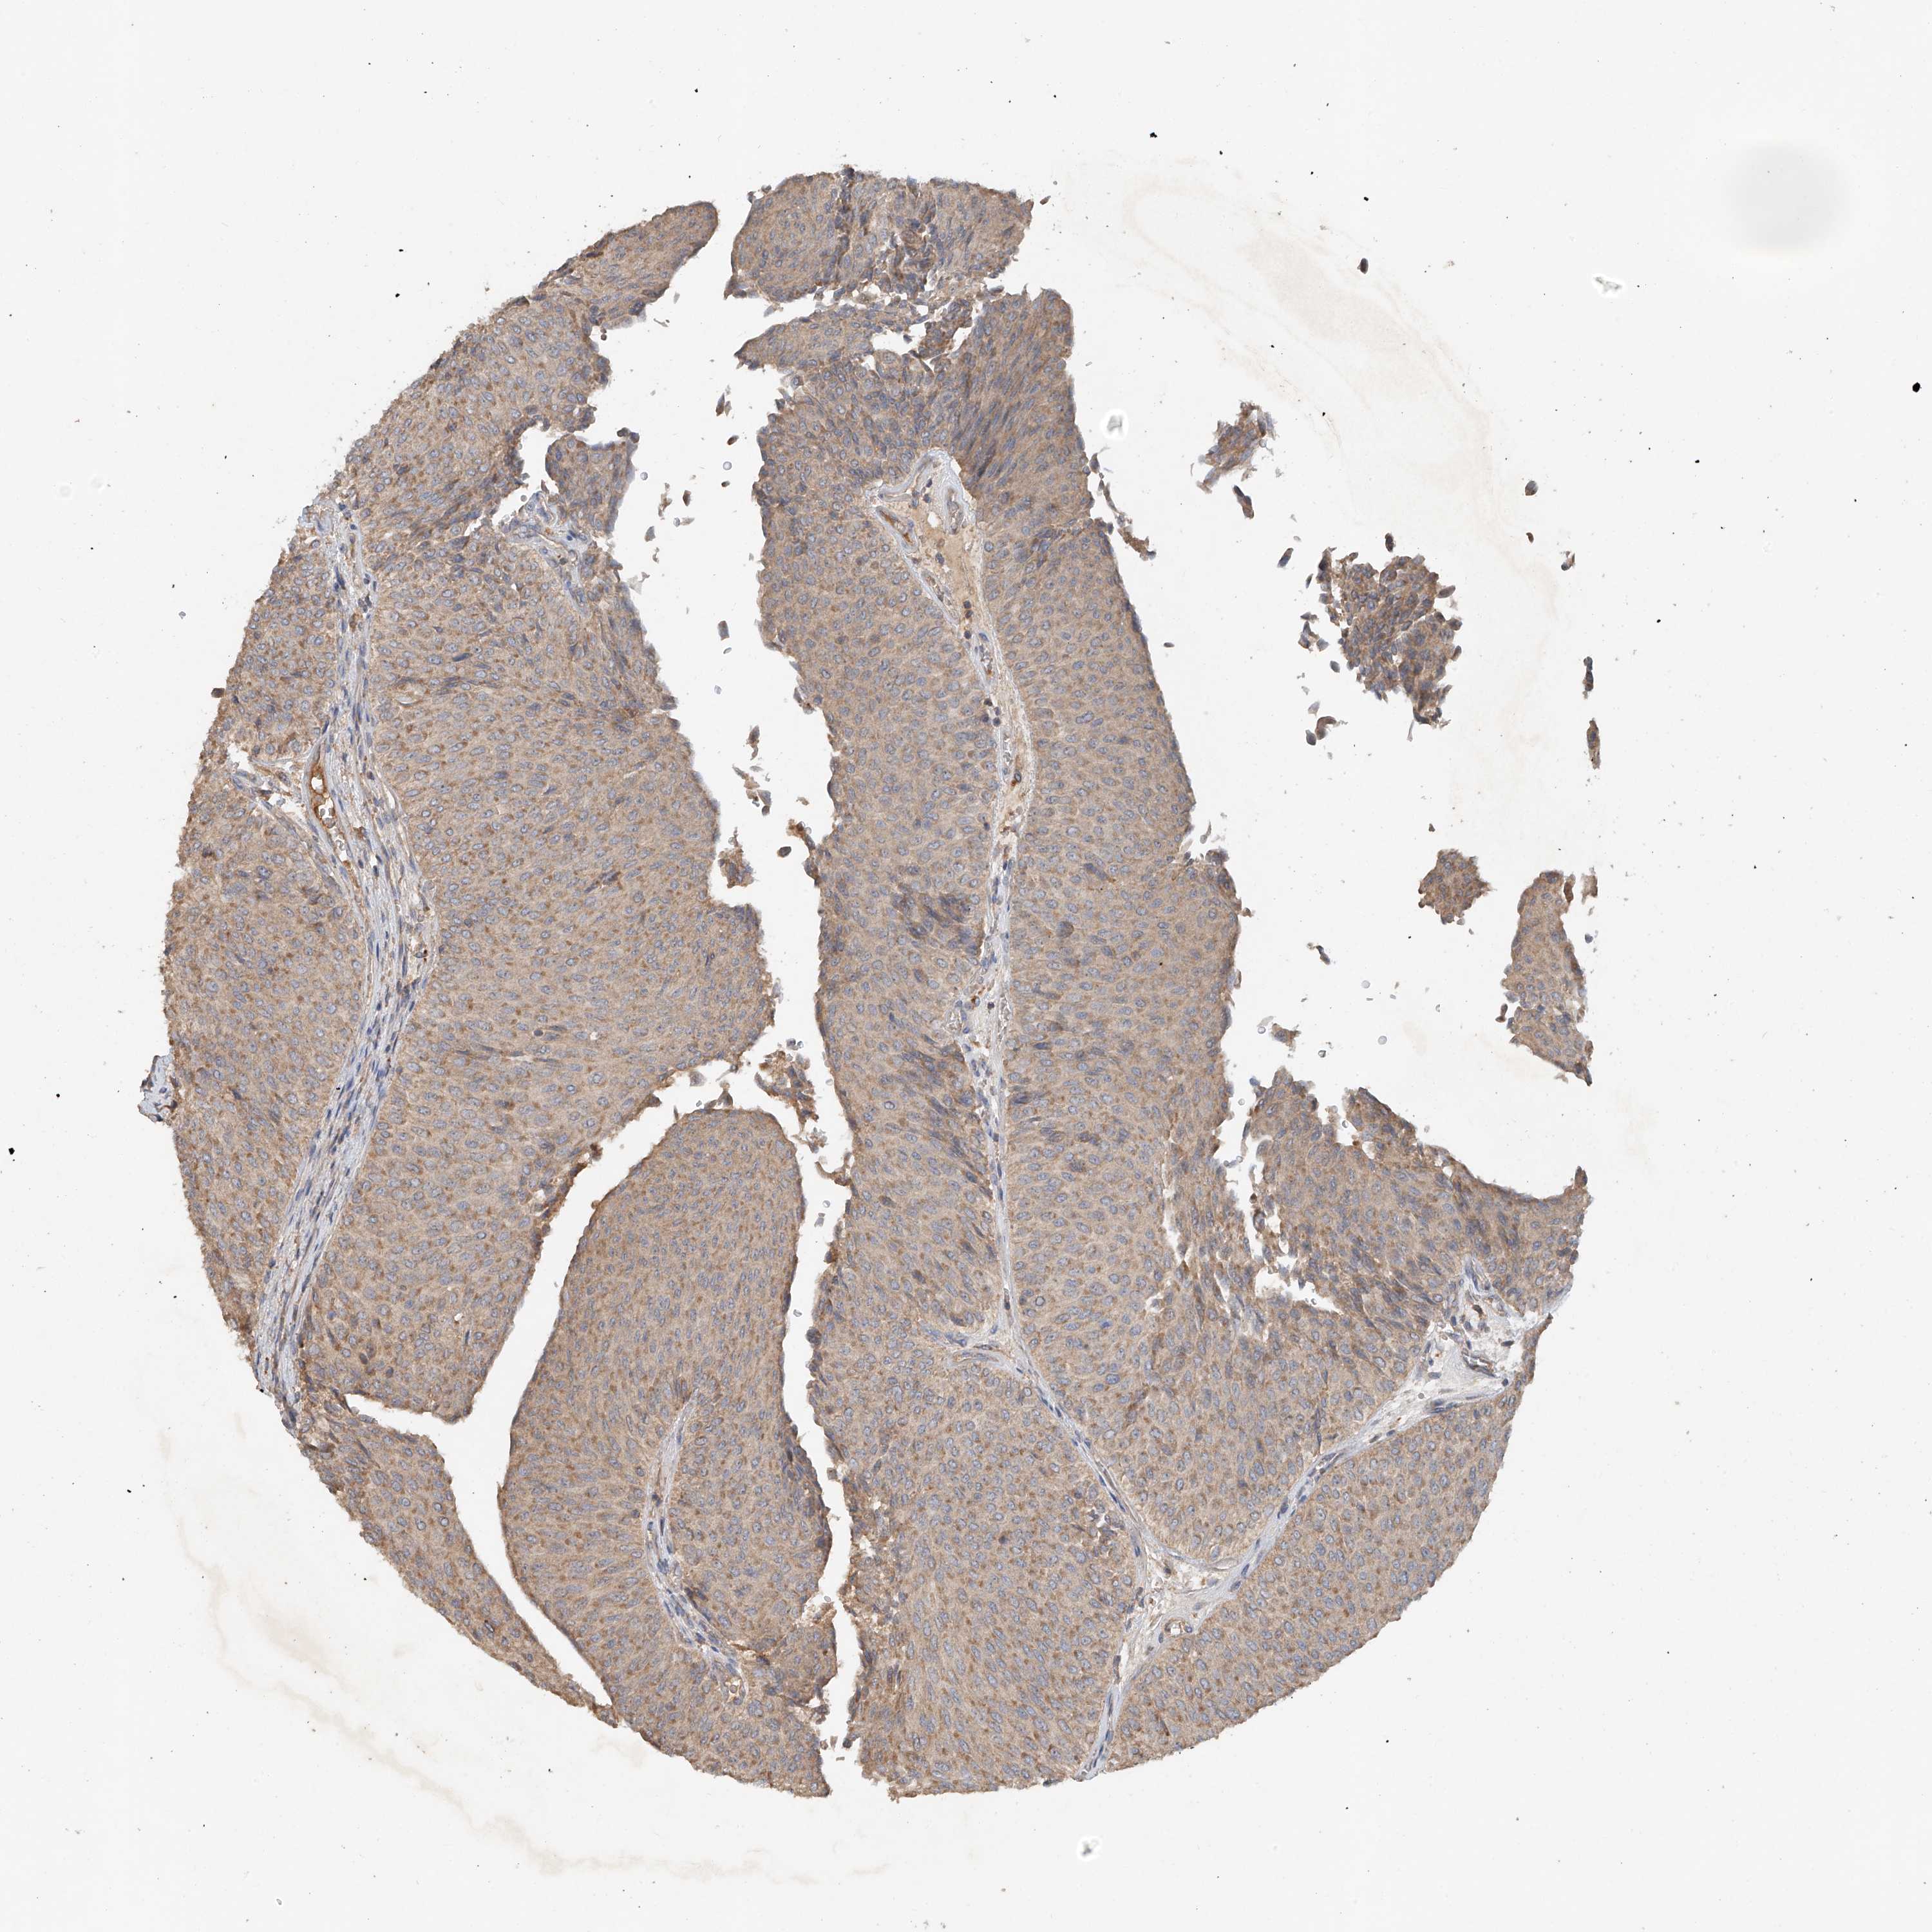

UROTHELIAL CANCER - Protein expressioni

A mouse-over function shows sample information and annotation data. Click on an image to view it in a full screen mode. Samples can be filtered based on level of antibody staining by selecting one or several of the following categories: high, medium, low and not detected. The assay and annotation is described here.

Antibody stainingi

Antibody staining in the annotated cell types in the current human tissue is reported as not detected, low, medium, or high, based on conventional immunohistochemistry profiling in selected tissues. This score is based on the combination of the staining intensity and fraction of stained cells.

Each image is clickable and will lead to virtual microscopy that enables deeper exploration of all samples and also displays staining intensity scores, fraction scores and subcellular localization as well as patient and tissue information for each sample.

Antibody HPA034627

Staining

High

Medium

Low

Not detected

Intensity

Strong

Moderate

Weak

Negative

Quantity

>75%

75%-25%

<25%

None

Location

Nuclear

Cytoplasmic/membranous

Cytoplasmic/membranous,nuclear

Urothelial carcinoma, Low grade

Urothelial carcinoma, High grade